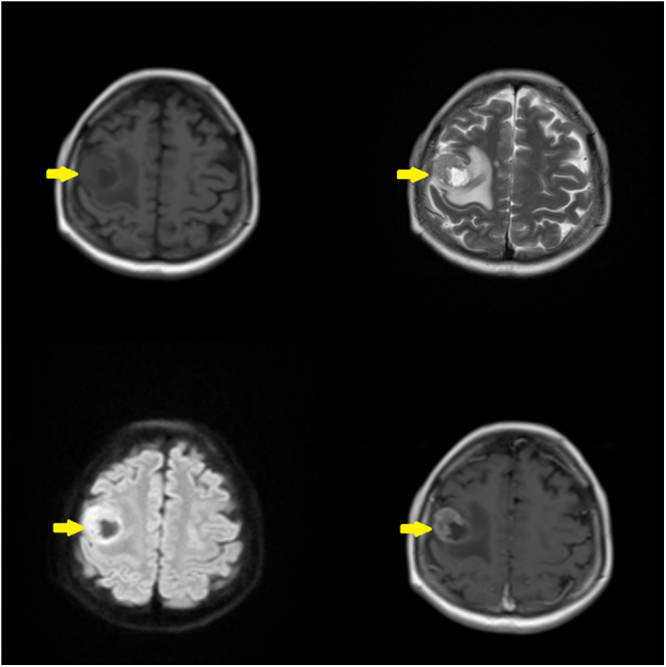

Case presentation: A 68-year-old Pakistani male with a prior diagnosis of LSCC presented with new-onset generalized tonic-clonic seizures. He had previously undergone total laryngectomy, radiotherapy, and chemotherapy. Brain MRI revealed a right frontal lobe lesion with surrounding edema, consistent with a solitary metastasis. Histopathology following craniotomy confirmed metastatic squamous cell carcinoma. The patient was managed with antiepileptics and referred for palliative whole-brain radiotherapy. He and his family opted for palliative care, declining further aggressive treatment.

Clinical discussion: Distant brain metastasis in LSCC is rare and may occur without prior systemic spread. The mechanism may involve perineural invasion, although the exact pathophysiology remains unclear. Current diagnostic approaches include MRI and FDG-PET/CT. Due to limited cases, standardized treatment protocols are lacking. Management options include surgery, radiotherapy, chemotherapy, and palliative care, depending on disease progression and patient preference. Seizures as a presenting symptom are uncommon but may indicate intracranial involvement.